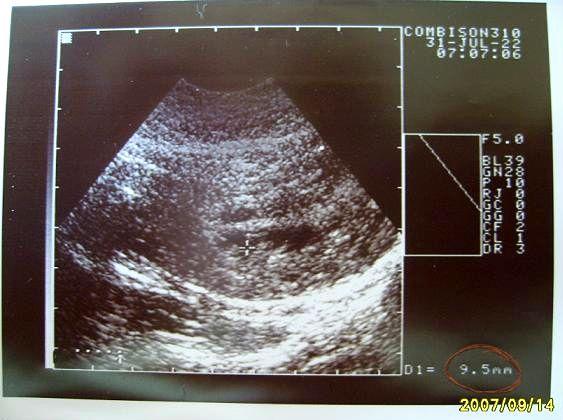

06+5 Bababogyó - CRL: 0,95 cm (07/07/17)